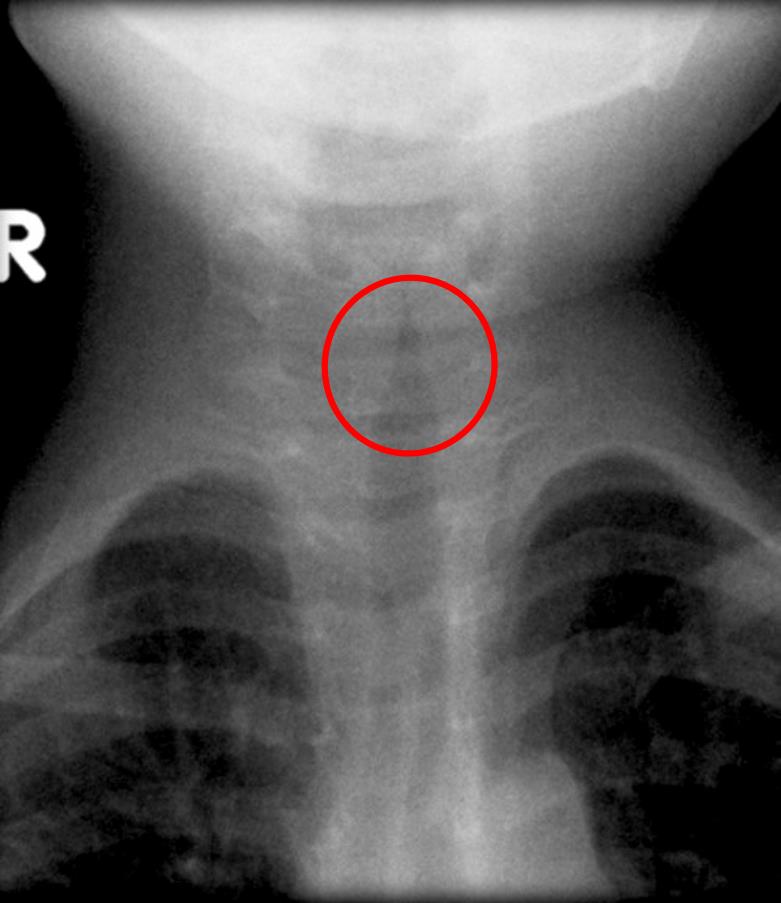

A 3-year-old boy is brought to the emergency department by his parents with a 2 day history of cough. His parents say that he developed a mild fever, runny nose, and a high-pitched, dry cough after they returned from a cruise. They became concerned earlier today when his parents noticed that his breathing became “noisy” particularly when he inhaled. This difficulty breathing persisted even during rest. He is otherwise healthy, is up-to-date on immunizations, and takes no medications. His temperature is 101.7°F (38.7°C), blood pressure is 100/70 mmHg, pulse is 140/min, and respirations are 34/min. Pulse oximetry on room air shows an oxygen saturation of 97%. The boy appears lethargic and a high-pitched inspiratory stridor is heard at rest. He exhibits nasal flaring and subcostal retractions. On auscultation, there are coarse breath sounds and diminished air movement bilaterally. Skin tone and turgor are normal. A chest radiograph is shown in Figure A. Which of the following is the most appropriate next step in management?

This patient with a fever, high-pitched cough, inspiratory stridor, respiratory distress, and a chest radiograph demonstrating subglottic narrowing, most likely has croup. Patients with severe croup should be treated with corticosteroids and nebulized epinephrine.

Figure/Illustration A is a chest radiograph highlighting subglottic narrowing, also known as the “steeple sign” (red circle). This finding is classically seen in patients with croup.